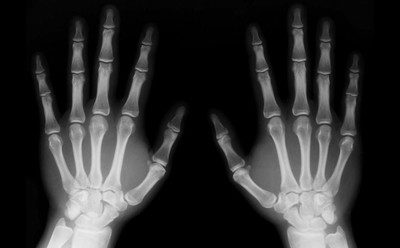

В 1895 году немецкий физик Вильгельм Рентген работал с катодно-лучевой трубкой. Несмотря на то, что сама трубка была экранирована, Рентген заметил, что картон, покрытый платиносинеродистым барием и находившийся рядом с трубкой, начинал светиться в темной комнате.

Рентген попытался блокировать лучи, но большинство вещей, которые он помещал перед ними, проявляли аналогичный эффект. Когда в конце концов он поставил перед трубкой свою руку, то заметил, что она начинает просвечиваться на изображении, проецируемом на экране. Свое открытие он назвал «икс-лучами» (X-rays). После Рентген заменил трубку фотографической пластиной и получил первую рентгенограмму.

Вскоре после этого технология была адаптирована медицинскими учреждениями и исследовательскими лабораториями. Однако опасность длительного воздействия рентгеновских лучей ученым еще только предстояло понять.